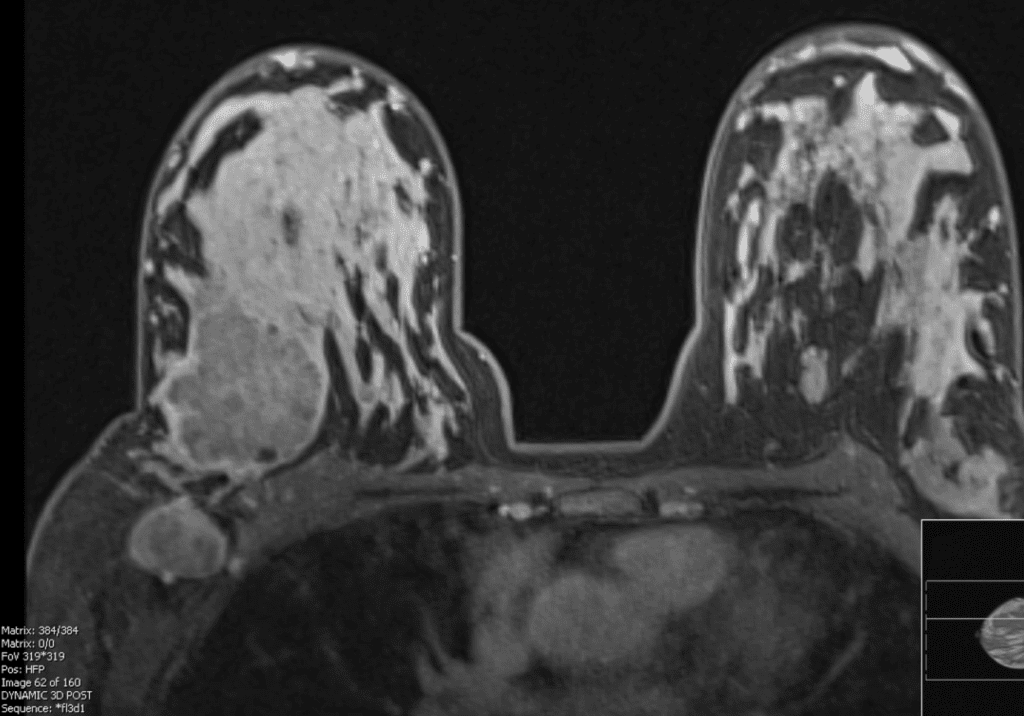

Patient two weeks postpartum with right breast cancer and abnormal lymph node visualized on MRI.

Patient six months postpartum with new lump right breast that was not well visualized on mammogram but appeared distinctly on MRI.